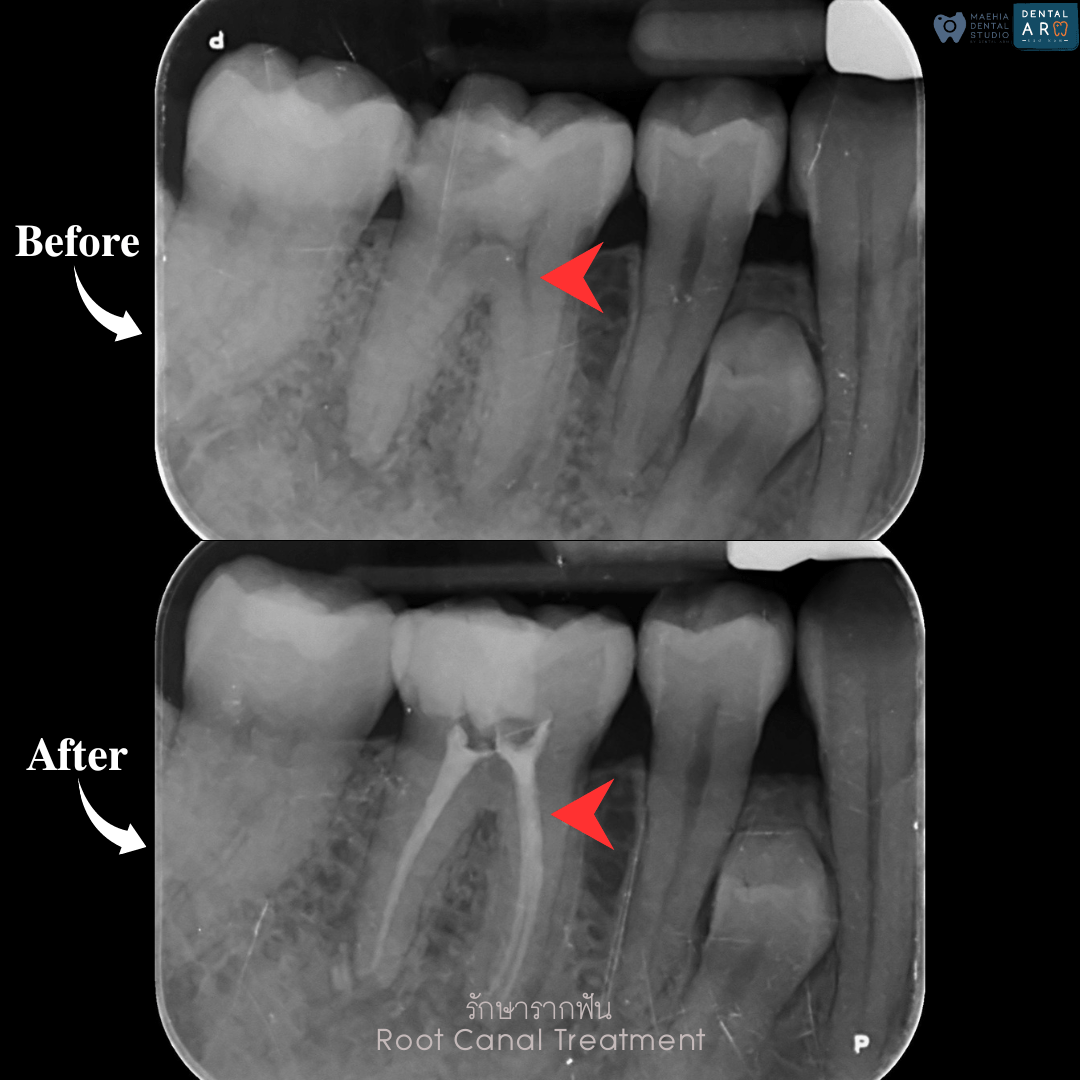

รักษารากฟัน

คือ การรักษาฟันที่เกิดการอักเสบและติดเชื้อภายในโพรงประสาทฟัน และเนื้อเยื่อรอบปลายรากฟัน อันมีสาเหตุมาการอักเสบและติดเชื้อภายในรากฟัน โดยทันตแพทย์จะทำการทำความสะอาดและใส่ยาในคลองรากฟัน และทำการอุดรากฟันเป็นขั้นตอนสุดท้าย การรักษารากฟันจะช่วยเก็บรักษาฟันให้สามารถคงอยู่ในช่องปากต่อได้ โดยไม่ต้องถอนฟันและไม่ต้องใส่ฟันทดแทน